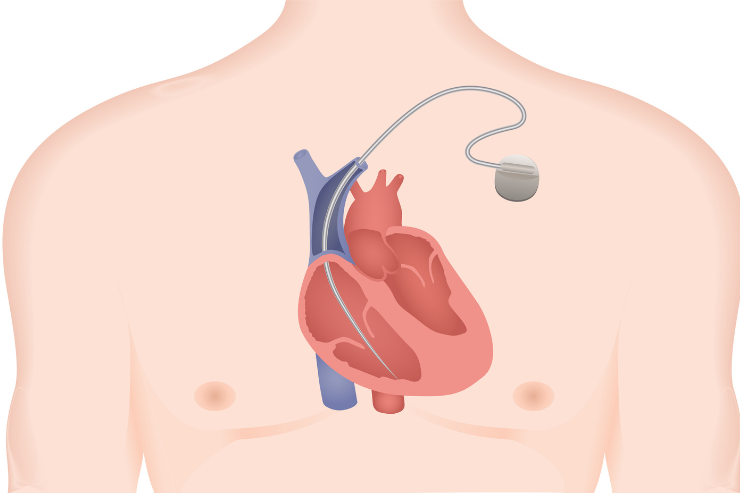

Cardiac Implantable Electronic Devices

Cardiac Implantable Electronic Devices (CIEDs) are advanced devices implanted to manage heart rhythm disorders. They include pacemakers to regulate slow heartbeats, Cardiac Resynchronization Therapy (CRT) to improve heart function, and Implantable Cardioverter-Defibrillators (ICDs) to prevent sudden cardiac arrest. CIEDs are crucial for maintaining proper heart rhythm and enhancing patient quality of life.